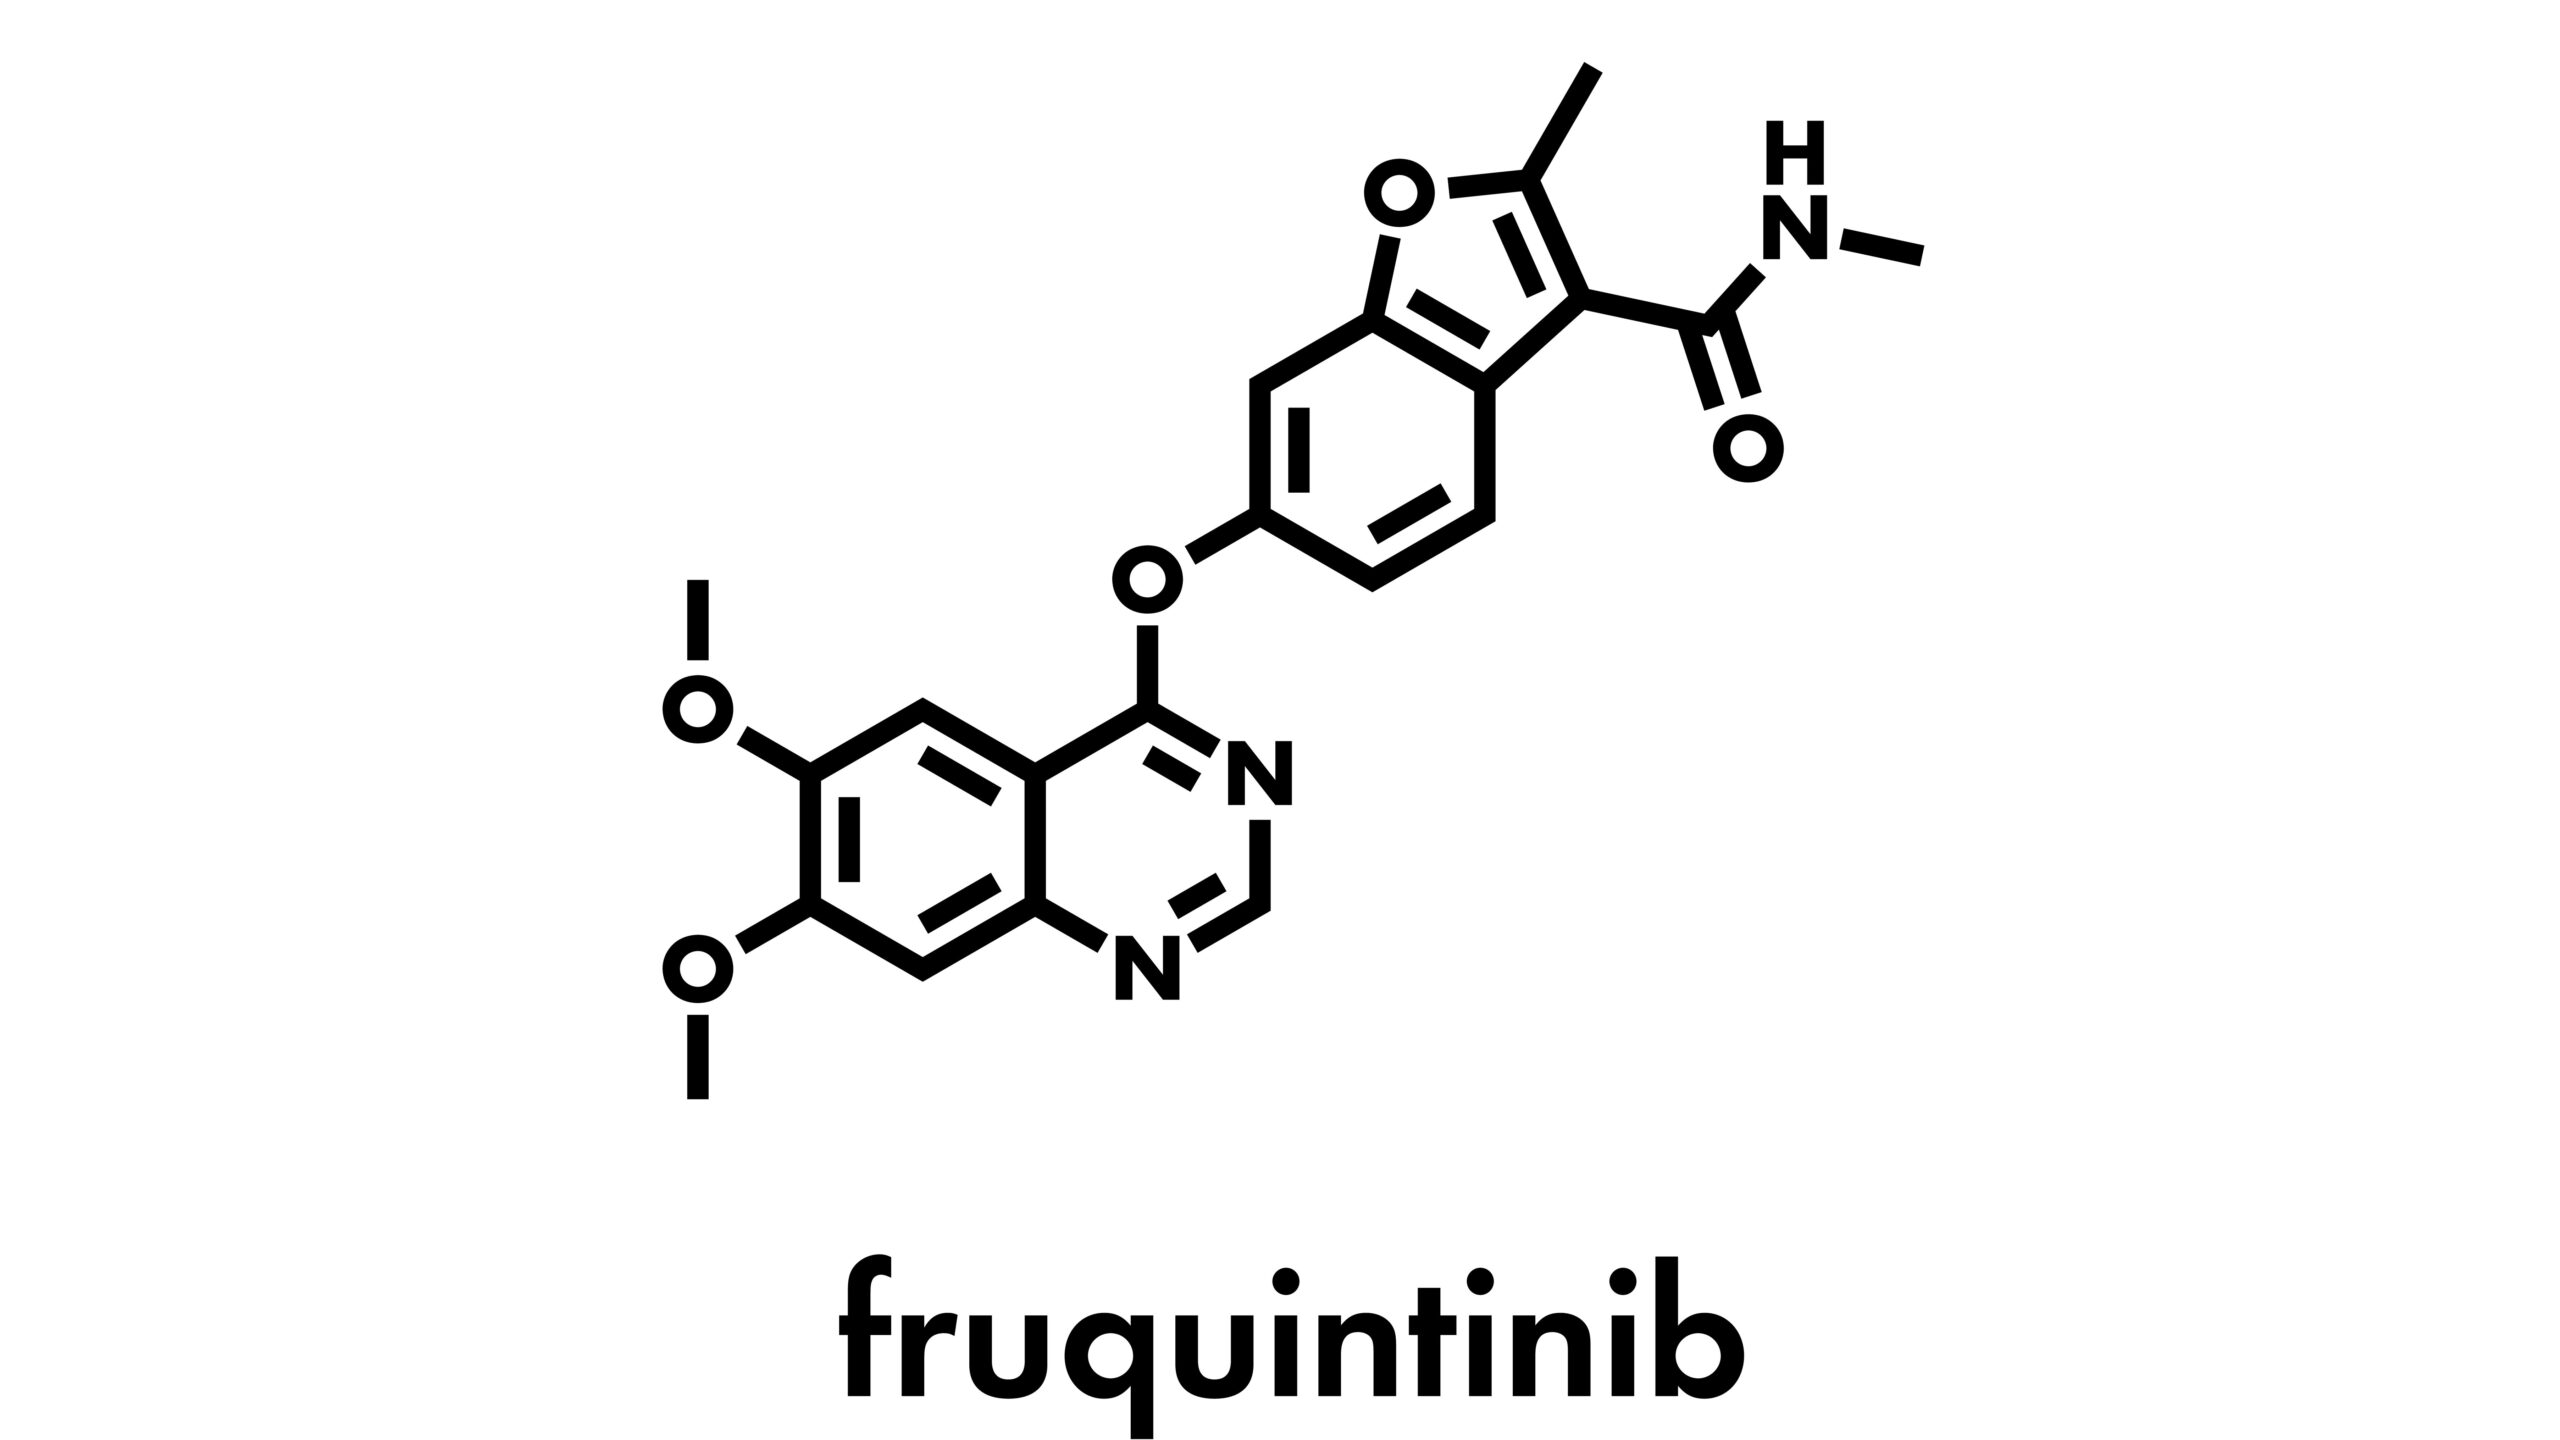

Fruquintinib meaningfully improved overall survival in patients with refractory metastatic colorectal cancer versus placebo.Patrick DalyColorectal Cancer | March 19, 2025